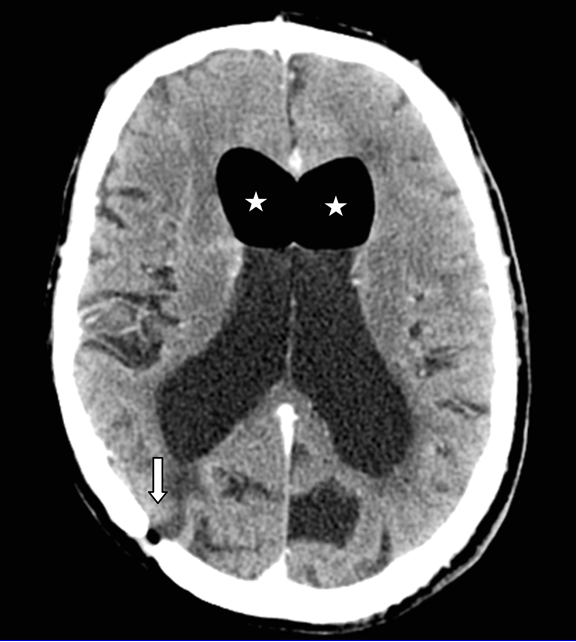

Magnetic resonance imaging (MRI) scan was performed which on the coronal images (Figure 2) demonstrated extension of the lateral ventricle to the temporal bone and localized ventriculitis and meningeal enhancement. The diagnosis of otogenic pneumocephalus, secondary to recurrent cholesteatoma with associated temporal bone CSF leak was made. Unfortunately, the patient developed fulminant meningitis whilst being prepared for surgery, which resulted in multiorgan failure despite maximal medical care and ultimately proved fatal.

Figure 2: Magnetic resonance imaging, T2-weighted fluid attenuated inversion recovery sequence.